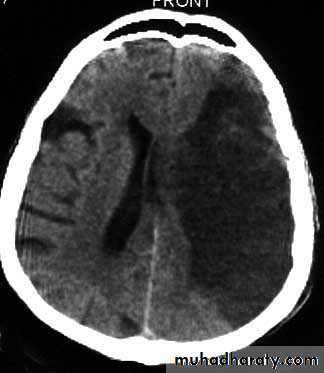

CT scan :-CT will be normal in early infarction (less than 6 hours).CT very sensitive for acute hemorrhage.